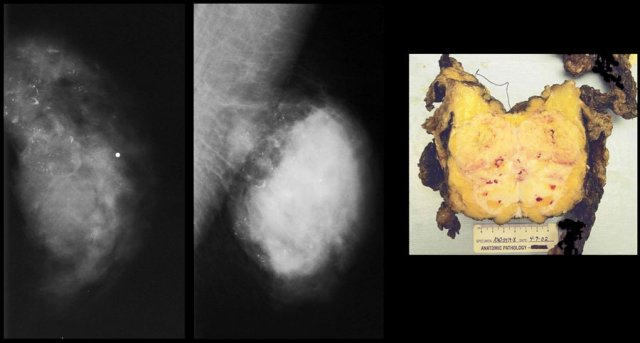

Invasive ductal carcinoma Invasive ductal carcinoma

On the left a huge invasive ductal carcinoma with some coarse benign looking calcifications.